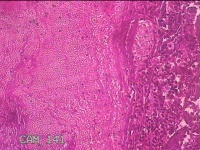

子宫左侧壁残留妊娠物

性别

女

年龄

40岁

临床诊断

稽留流产 药流失败 宫腔粘连

一般病史

停经5月余,要求终止妊娠。

标本名称

大体所见

灰白暗红色不规则碎组织1.5x1.3x0.3cm一堆,内有少许绒毛样组织。

见胎盘绒毛。

凝血中见退 变蜕膜和机化绒毛。